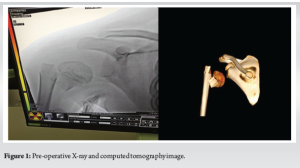

A 5-year-old right-hand dominant girl presented to the emergency department after falling approximately 5 ft from the second birth of a train onto her outstretched left hand, resulting in severe pain and visible shoulder deformity. She experienced immediate swelling and inability to move her left arm but had no loss of consciousness or other injuries. On examination, the left shoulder appeared grossly deformed with a visible sulcus sign, extensive swelling, and ecchymosis. The patient held her arm in slight abduction and external rotation, refusing movement due to pain. Neurovascular examination revealed intact distal pulses and no sensory or motor deficits. Radiographs revealed a severely displaced proximal humerus fracture with anterior glenohumeral dislocation. CT confirmed a Neer-Horwitz Type IV fracture with significant displacement and varus angulation (Fig. 1).